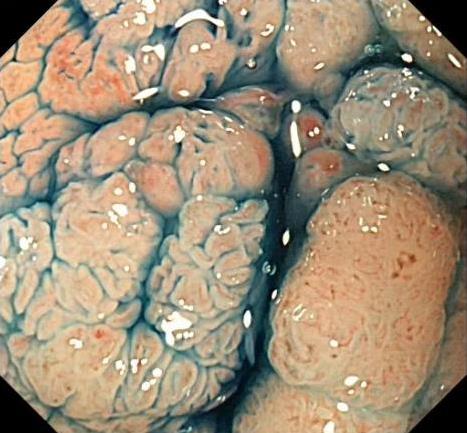

• 色素内镜和窄带成像技术联合放大内镜对早期结直肠癌及癌前病变的诊断价值研究

摘要:目的 探究色素内镜(CE)和窄带成像技术(NBI)联合放大内镜(ME)对早期结直肠癌及癌前病变的诊断价值研究。方法 选取2023年8月-2024年7月于该院接受检查的疑似早期结直肠癌及癌前病变的患者160例。采用四格表法,分析NBI-ME和CE-ME检测早期结直肠癌及癌前病变的敏感度、特异度和准确度;采用Kappa一致性检验,分析CE-ME和NBI-ME诊断早期结直肠癌及癌前病变与病理检查的一致性。结果 病理结果显示,良性病变52例,癌前病变90例,结直肠癌18例。CE-ME检测结果显示,良性病变43例,癌前病变101例,结直肠癌16例,漏诊率为33.33%;CE-ME诊断早期结直肠癌及癌前病变与病理检查的一致性中度(Kappa = 0.605,P < 0.01),敏感度为66.67%,特异度为97.18%,准确度为93.75%。NBI-ME检查结果显示,良性病变43例,癌前病变100例,结直肠癌17例,漏诊率为16.67%,NBI-ME诊断早期结直肠癌及癌前病变与病理检查的一致性较高(Kappa = 0.714,P < 0.01),敏感度为88.33%,特异度为98.59%,准确度为96.88%。CE-ME与NBI-ME两者联合检查结果显示,良性病变56例,癌前病变86例,结直肠癌18例,漏诊率为5.56%,两者联合诊断早期结直肠癌及癌前病变与病理检查的一致性极高(Kappa = 0.857,P < 0.01),敏感度为94.44%,特异度为99.30%,准确度为98.75%,高于CE-ME和NBI-ME单独检查。结论 CE和NBI联合ME对早期结直肠癌及癌前病变具有较高的诊断价值。值得应用于临床。